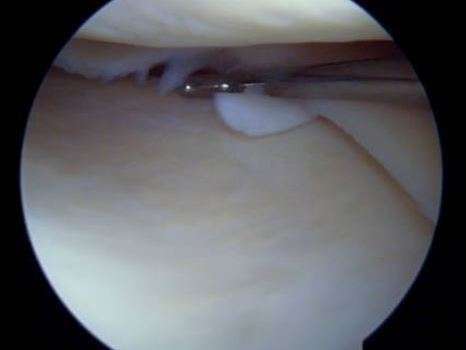

La plupart du temps, les lésions méniscales traumatiques sont traitées chirurgicalement. Deux gestes sont possibles : la réparation méniscale et la méniscectomie. Ces deux interventions sont réalisées au cours d’une arthroscopie et ont des indications spécifiques à chacune.

Nous différencions trois zones. Une « rouge-rouge », au contact de la capsule articulaire (en périphérie), bien vascularisée, qui peut être suturée, surtout chez le jeune. Une zone « rouge-blanche » médiane, qui est moins cicatrisable, car moins bien vascularisé. Et une zone « blanche-blanche » (en profondeur), faiblement vascularisée, et par conséquent rarement suturée.